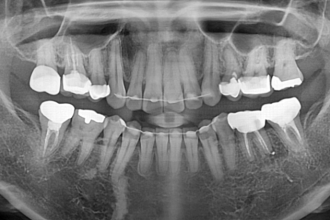

임플란트